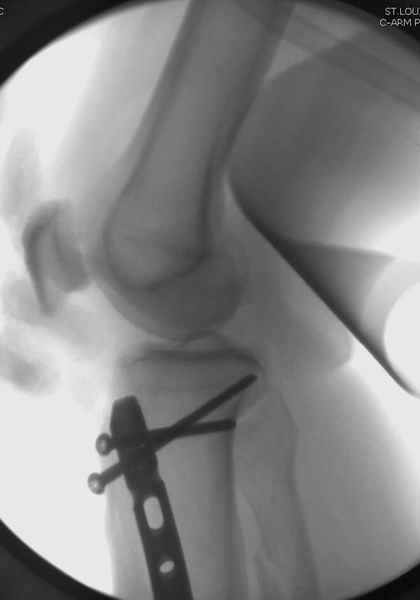

Здесь мы использовали новый Synthes Nail с дополнительными дырками, в проксимальной части 4: по две косых и поперечные (один стандартный а другой динамический), в дистальной части две поперечные, прямая и косая. Вес больного более 120 кг, нагрузку начнем через месяц.

Получилось красиво, поздравляю. Вверху можно было ограничиться одним винтом во фронтальное статическое отверстие, зачем два 45-градусных?

При такий спирали задний край tibia может быть сломан - нет ли этого в данном случае? На всякий случай можно было ввести 1-2 винта 4,5 мм спереди назад мимо гвоздя. Хотя самый дистальный блокирующий винт, возможно, зацепил этот отломок. А какой тут диаметр гвоздя и locking винтов?